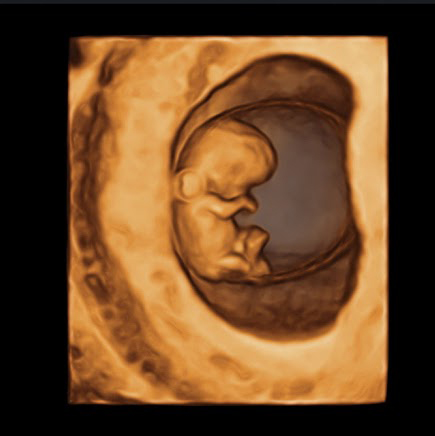

אולטרסאונד הראשון בהריון

זוהי בדיקת אולטרסאונד שניתן לעשות בין השבועות 12-6 להריון

בדיקה שבה נבדקים המיקום של שק ההריון (בתוך הרחם או מחוצה לו), הדופק של העובר, מספר העוברים, וגיל ההריון. הבדיקה נעשית בגישה נרתיקית